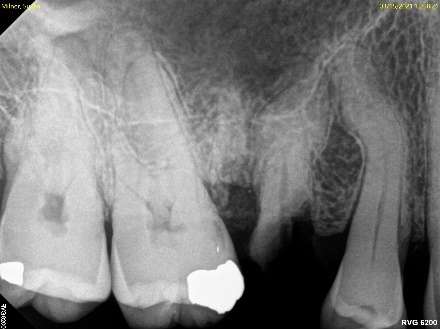

Fig. 1: Broken Tooth